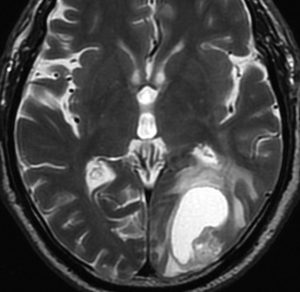

高齢者に発生したグリオーマです。左はガドリニウム増強MRIといいます。腫瘍の周囲が白く縁取られるように見えます。でも,右側のT2強調画像では,白く滲む部分が周囲に広がっています。

グレード3(かつての退形成性星細胞腫)かグレード4(膠芽腫),おそらく膠芽腫と「予想」できる画像です。確実ではないのですが,この予想は治療計画の上で重要なものです。